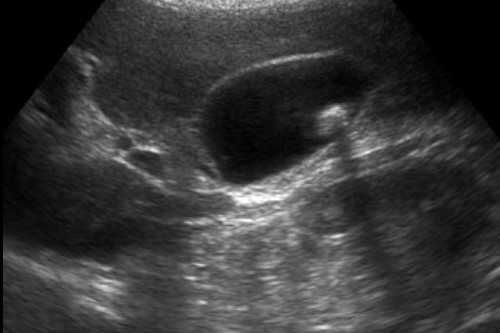

Ecografia

Mi occupo con passione di ecografia e di ecocolor-Doppler per la valutazione della patologia di collo, addome, pelvi, apparato muscoloscheletrico e dei vasi. L'ecografia è una metodica indolore e sicura che permentte di ottenere diagnosi accurate di numerosi distretti come fegato, colecisti, reni, pancreas, milza, aorta, tiroide, prostata, vescica, muscoli e strutture tendinee.